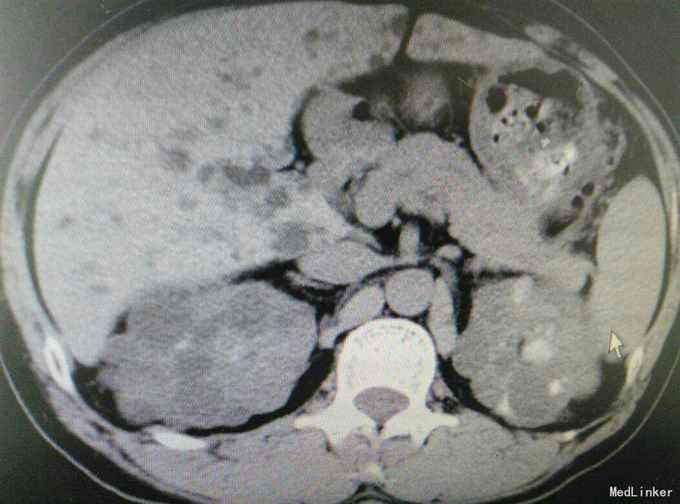

多囊肾合并双肾结石并积水

肾结石 多囊肾 多囊肝

患者47岁,男,因‘’腰痛伴、血尿伴发热7天‘入院。 患者既往有‘高血压’病史多年,7天前无明显诱因出现腰痛,随后出现肉眼血尿,为程肉眼血尿,当天晚上出现发热,最高体温38.6摄氏度,予以对症处理后,发热可退去,但症状反复,患者为求进一步进一步治疗遂来我院。

多囊肾,双肾结石,多囊肝,高血压